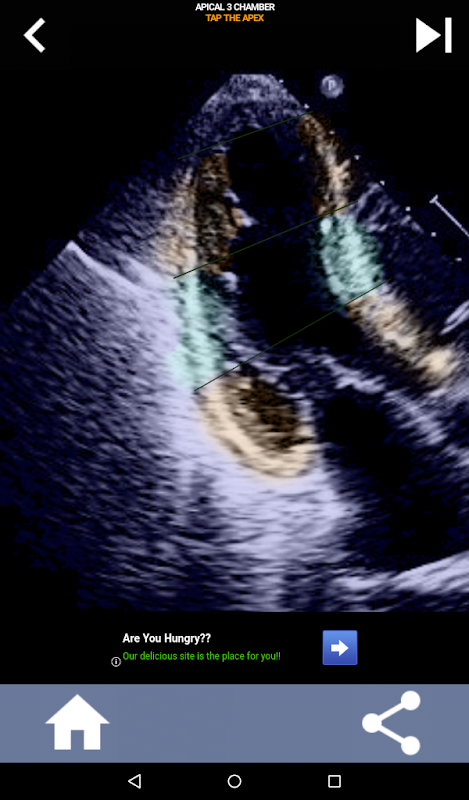

AHA دل کے حصوں کو سیکھنے کے لئے کوئز پر مبنی بصری نقطہ نظر: ایکو کارڈیوگرافی۔

AHA (امریکن ہارٹ ایسوسی ایشن) کے دل کے حصوں کو سمجھنا کارڈیک سونوگرافر کے لیے انتہائی اہمیت کا حامل ہے تاکہ وہ رپورٹ لکھنے والے ماہر امراض قلب کے ساتھ مؤثر طریقے سے بات چیت کر سکے۔ مخصوص جسمانی خطوں اور ان کے متعلقہ حصوں کو جان کر، سونوگرافر کسی بھی غیر معمولی باتوں یا نتائج کو درست طریقے سے بیان اور بات چیت کرسکتا ہے، دونوں پیشہ ور افراد کے درمیان واضح اور جامع مواصلت کو یقینی بناتا ہے۔

یہ تفہیم خاص طور پر اس وقت اہم ہو جاتی ہے جب ماہر امراض قلب کسی مسئلے کے صحیح محل وقوع کا پتہ لگانے کی کوشش کرتا ہے یا جب کال پر ڈاکٹر کسی مخصوص علاقے میں کسی مسئلے کی نشاندہی کرتا ہے، سونوگرافر کو متعلقہ طبقہ کو درست طریقے سے ظاہر کرنے کا اشارہ کرتا ہے، جیسے کہ درمیانی کمتر دیوار۔ اس طرح، AHA دل کے حصوں کی ایک جامع گرفت کا حامل ہونا ضروری مہارت کا مجموعہ ہے۔

یہ ایپ اصل ایکو امیجز کا استعمال کرتے ہوئے آپ کے علم کی جانچ کرے گی، جو مجھے اکثر پڑھانے کا بہترین طریقہ معلوم ہوتا ہے۔